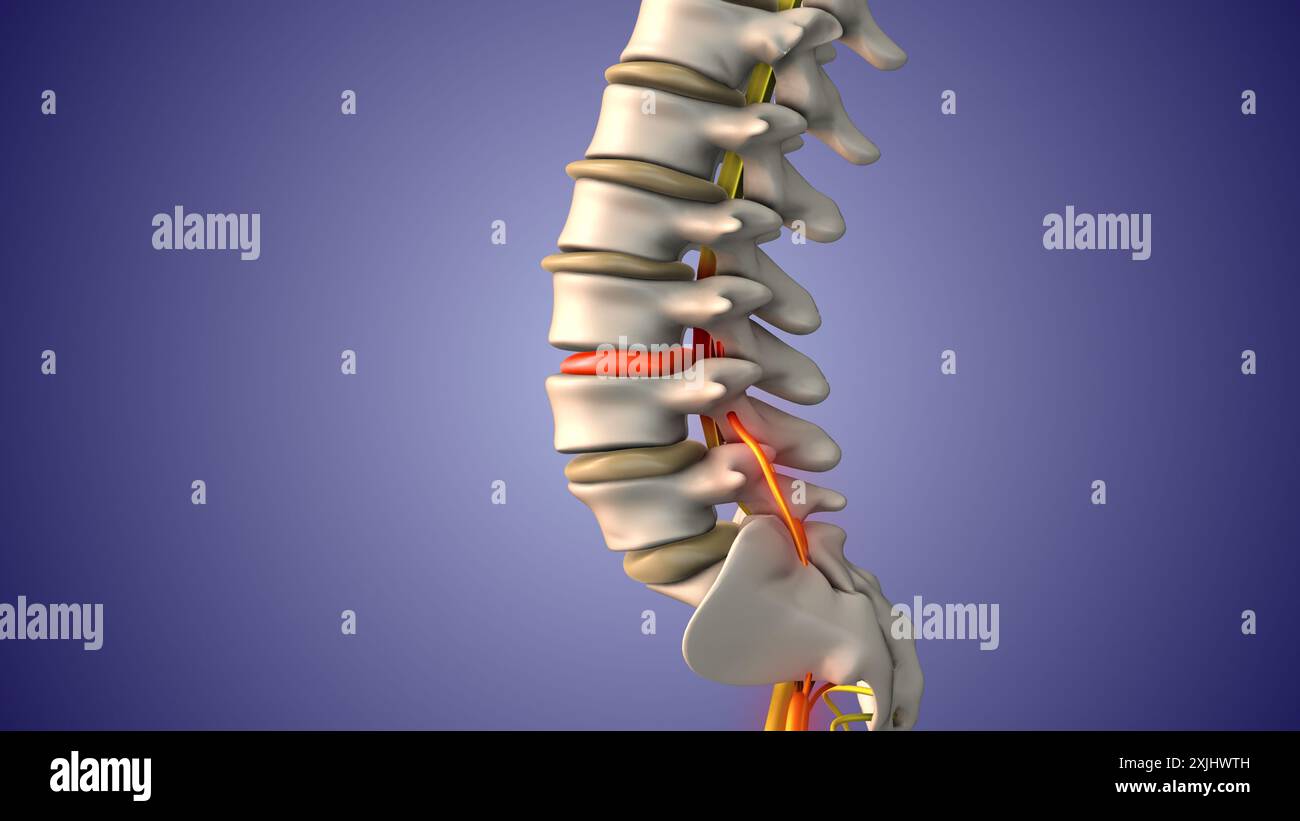

Douleur du nerf sciatique par hernie discale Banque D'Imageshttps://www.alamyimages.fr/image-license-details/?v=1https://www.alamyimages.fr/douleur-du-nerf-sciatique-par-hernie-discale-image613820161.html

Douleur du nerf sciatique par hernie discale Banque D'Imageshttps://www.alamyimages.fr/image-license-details/?v=1https://www.alamyimages.fr/douleur-du-nerf-sciatique-par-hernie-discale-image613820161.htmlRF2XJHWTH–Douleur du nerf sciatique par hernie discale

Douleur du nerf sciatique dans le bas du corps Banque D'Imageshttps://www.alamyimages.fr/image-license-details/?v=1https://www.alamyimages.fr/douleur-du-nerf-sciatique-dans-le-bas-du-corps-image613820164.html

Douleur du nerf sciatique dans le bas du corps Banque D'Imageshttps://www.alamyimages.fr/image-license-details/?v=1https://www.alamyimages.fr/douleur-du-nerf-sciatique-dans-le-bas-du-corps-image613820164.htmlRF2XJHWTM–Douleur du nerf sciatique dans le bas du corps